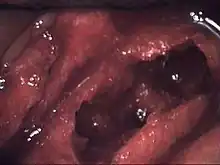

| Osteonecrosis of the jaw of the upper left jaw in a patient diagnosed with chronic venous insufficiency | |